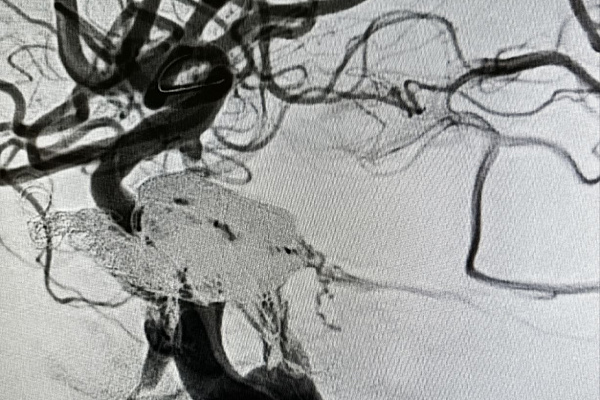

Чтобы исправить ситуацию, Максиму Бессмертных предстояло восстановить целостность поврежденной сонной артерии. Впервые в своей практике для лечения фистулы он использовал комбинацию двух видов эмболизирующего материала, сформировав новую стенку сосуда из специальной микроспирали и жидкого эмболизата. На создание каркаса в месте разрыва артерии ушло более двух метров спирали. Затем пространство между её завитками подобно монтажной пене заполнил композитный материал из биосовместимого полимера и порошка тантала.

Малоинвазивное рентгенэндоваскуляное вмешательство выполнялось без разрезов. Доступ всего инструментария и материала к «рабочей зоне» обеспечивался через два прокола - артерии в паховой области и яремной вены на шее. Как и любая операция на сосудах головного мозга, эта была сопряжена с высокими рисками, поэтому требовала ювелирной точности и предельной осторожности. Этим обусловлена её длительность – около пяти часов.

Рентгенохирург успешно провёл сложнейшую реконструкцию фрагмента левой сонной артерии и разделил потоки артериальной и венозной крови. Полноценное питание головного мозга возобновлено. С положительной динамикой пациент выписан под наблюдение.